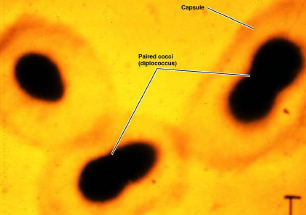

Mycobacterium (分枝桿菌屬)

- 需氧

- 長很慢(20hrs 分裂)

- 非典型G+

- 細胞壁含有過多的脂類,無法直接用水溶性染劑做染色

- carbolfuchsin 染,酸性酒精脫色

- acid fast stain +

- 不產生外毒素,靠免疫

- 細胞壁

- Mycolic acid

- Lipoarabinomannan(LAM)

- 類似 O antigen

- 類似 O antigen